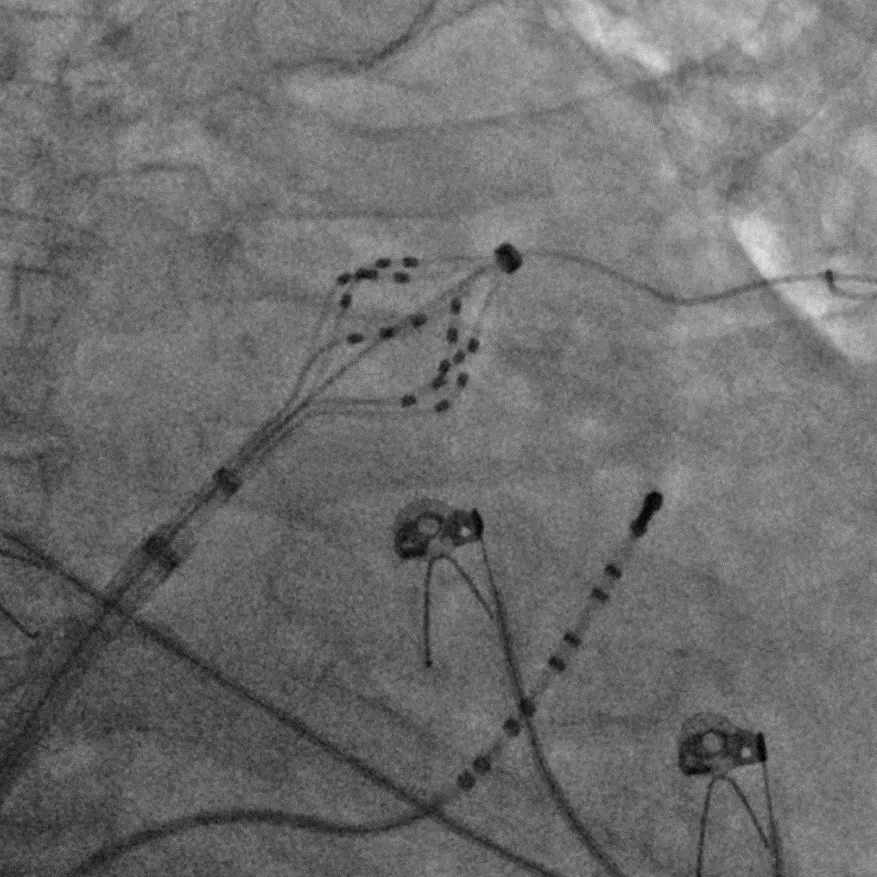

六瓣花导管呈网篮及花瓣形态放电

LSPV消融及前后电位对比

LIPV消融及前后电位对比

RSPV消融及前后电位对比

RIPV消融及前后电位对比

后壁消融及前后电位对比

上腔静脉消融及前后电位对比